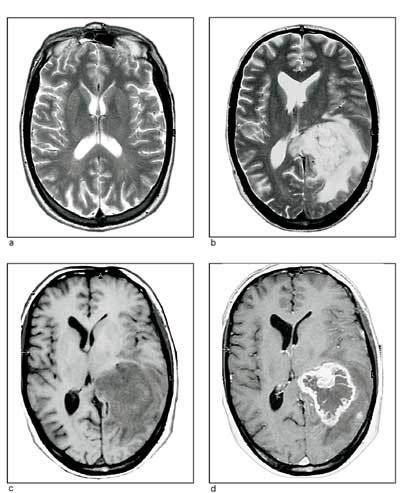

Hjernemetastaserer vanligere enn primære intrakraniale svulster, men i kirurgiske serier av hjernesvulster utgjør de bare 10 – 12 %. Primærsvulsten er som regel lokalisert i bronkiene, bryst, mage og tarmkanal, urinveier, genitalia og hud (melanom), i denne rekkefølgen. På MR er hjernemetastasene som regel runde, velavgrensede, homogent utseende, kontrastoppladende og omgitt av et kraftig ødem.

Primære maligne lymfomer

Disse debuterer ofte med multifokale periventrikulære lesjoner, og de sprer seg sjelden ekstrakranialt. Kliniske og radiologiske tegn på primært hjernelymfom kan forbigående forsvinne etter steroid- eller strålebehandling. Prognosen er likevel dårlig, med raskt residiv. Median overlevelse er ca. ett år, femårsoverlevelsen 10 – 20 % etter strålebehandling alene. Systemisk og intratekal metotreksat i kombinasjonskurer med bl.a. cytarabin synes å forbedre prognosen (40).